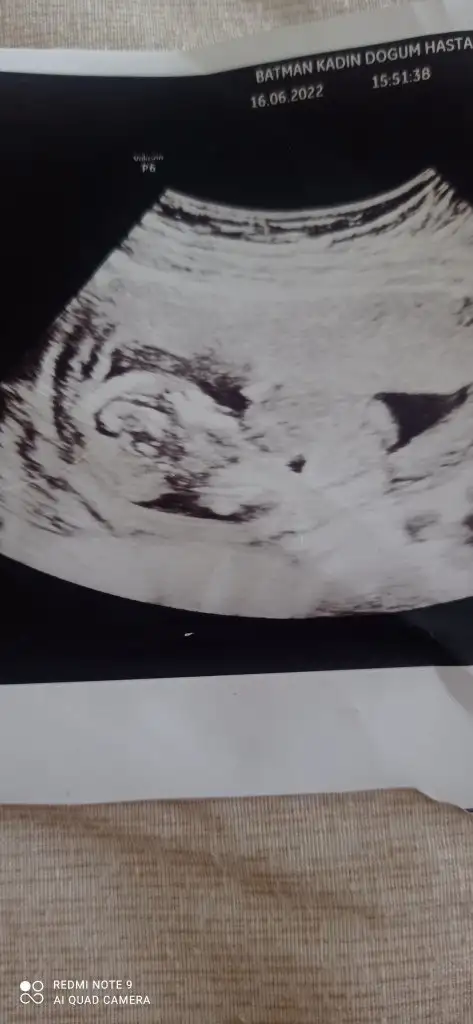

Merhaba bugün gittim kontrole önce göstermiyo dedi doktor sonra kız gibi dedimaşallah prenses gibi duruyorbende 17+5 im daha öğrenemedim

tahmin yine tuttuMerhaba bugün gittim kontrole önce göstermiyo dedi doktor sonra kız gibi dedi

5 ve 14. haftaya kadar olan ultrason fotolarınızı paylaşın. Vajinadan mı yoksa karından mı çekildiğini ve kaç haftalık olduğunu da mutlaka belirtin.